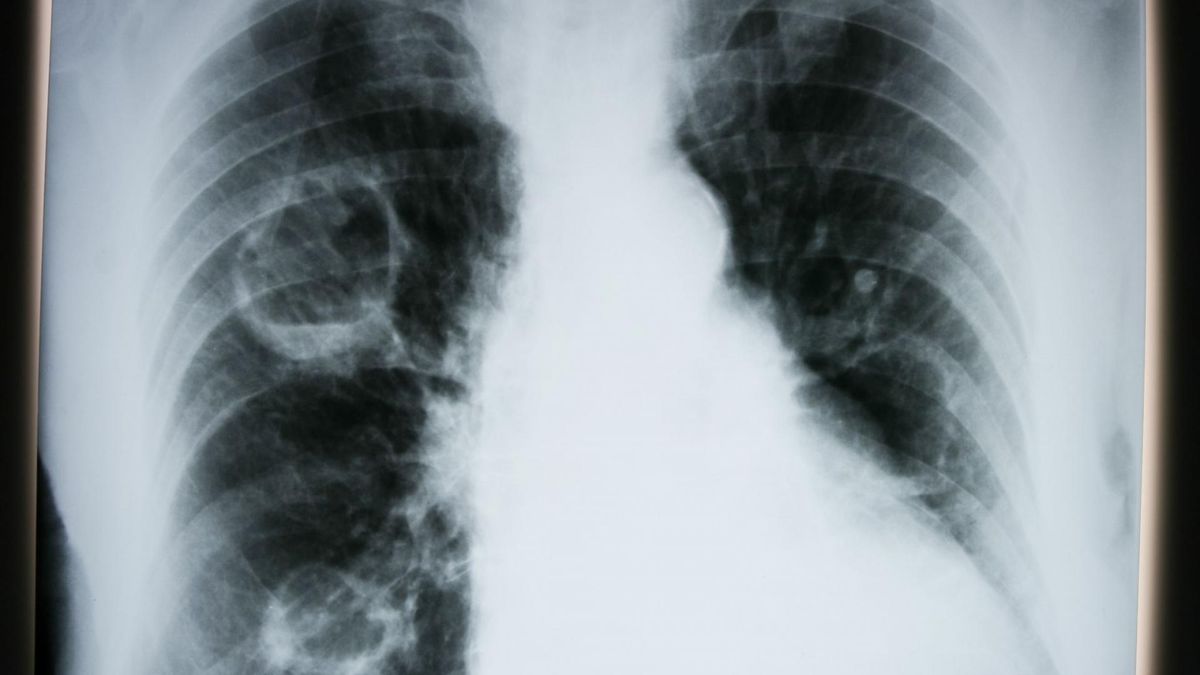

Dokładny przebieg zakażenia pokazują lekarze z USA. Medycy ze Szpitala Uniwersyteckiego im. Jerzego Waszyngtona udostępnili film, który obrazuje spustoszenie płuc w wyniku zakażenia koronawirusem u 59-letniego pacjenta. Wirus w krótkim czasie zaatakował oba płuca mężczyzny.

Fragmenty zaznaczone na żółto to obszar płuc, w którym rozwinął się stan zapalny.

"U pacjentów demonstrujących tak duże zmiany uszkodzenia płuc postępują szybko i obejmują duży obszar. Zniszczone w tym stopniu płuca będą goić się długo. Dla 2 do 4 proc. osób z COVID-19 nie będzie pomocy" - tłumaczy dr Keith Mortman szef torakochirurgii w Szpitalu Uniwersyteckim im. Jerzego Waszyngtona. "Pokazujemy to wideo, by ludzie zrozumieli, że nasze prośby o unikanie tłumów, izolację - mają sens. Ludzie muszą tę chorobę traktować serio" - dodaje lekarz.